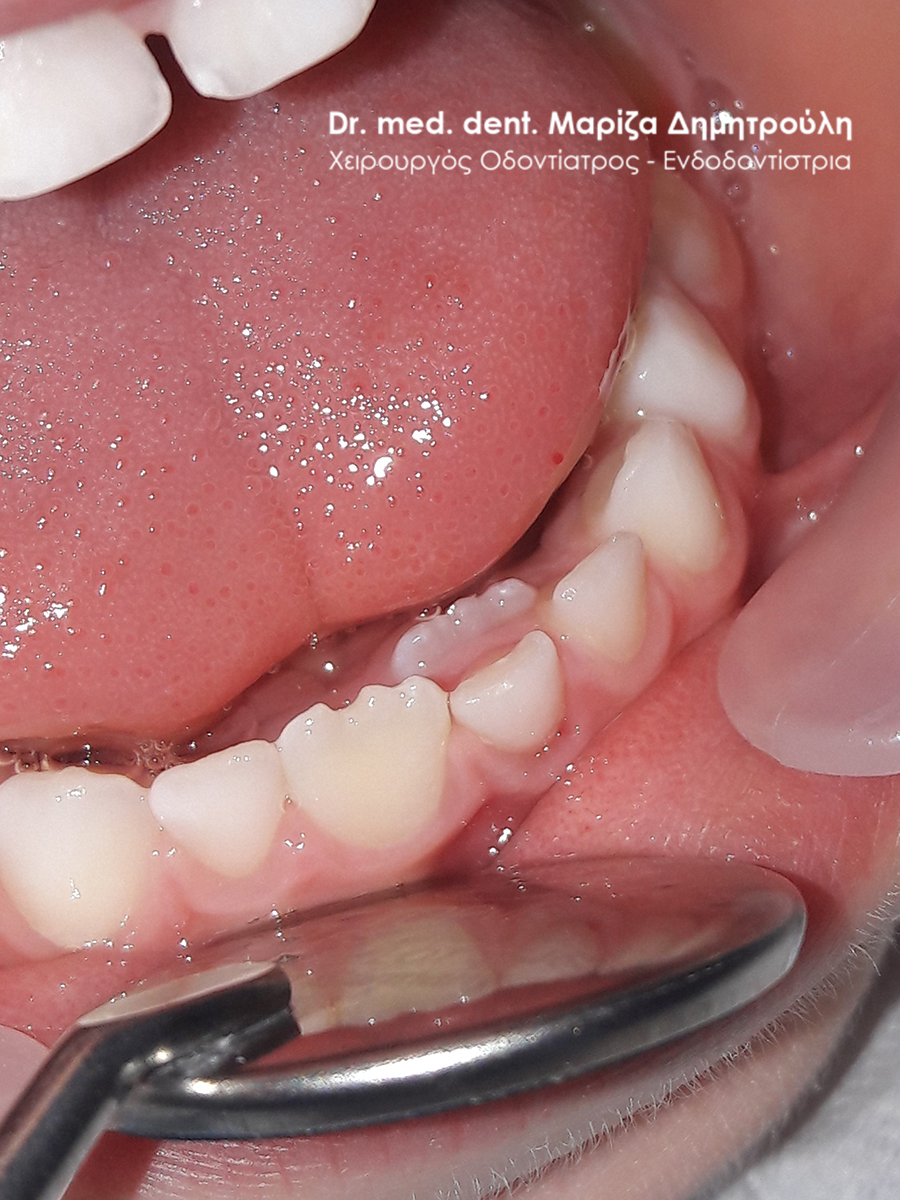

BEFORE